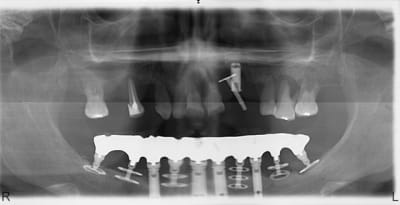

Une de tes patientes est venue me rendre visite hier, à l'époque elle avait vendu la villa pour faire le travail

Pourquoi tant de titane ?

je sais pas si c'est du pépé....en tout cas là, y a plusieurs disks qui pataugent dans la merde....

c'est vrai y a pas de parodontite mais une péri-implantite.

Tiens voilà justement un cas pour ceux qui sont convaincus que les implants maintiennent le volume osseux.

Dans le cas posté, les parties latérales ne présentent aucunes dents ni implants et pourtant le niveau osseux est conservé contrairement à la region antérieure implantée !

1ère chose : observe le caractère incomplet de l arcade supérieure et demande toi ce que cette patiente a fait pour manger...Elle n a utlisé que certains endroits et pas l intégralité des arcades d où certains dégâts notoires à certains endroits

2ème chose : son état parodontal est tel à l arcade supérieure qu elle contaminé toute sa bouche avec des germes disons assez aggressifs...

Néanmoins ce déséquilibre parodontal et mécanique n explique pas tout...Allons y point par point

47 Implant ok et note bien que de ce côté il manque le plus de dents à l arcade sup donc elle s est servie de l autre côté

46 le double disk voit son disk crestal exposé mais l apicla est ok... Il ne faut pas déposer l implant mais éliminer le disk crestal simplement... Même si le double disk apporte un grand blocage primaire, on poserait actuellement un simple disk à cet endroit car cela diminue le risque de perte osseuse en crestal

36 Surcharge unilatérale exagérée il faut éliminer l implant

37 Surcharge et zone de flexion ont eu raison de ce disk trop peu enfoui ds l os Il faut l éliminer

De plus ces simples et ces doubles disks appartiennent à une génération de disk qui furent réalisés en état de surface microrugueux càd SLA ( sablé + attaque acide )... Totalement abandonnés pour revenir à du lisse d usinage qui pose bien moins de problème d abrasion d os au contact de cette surface....